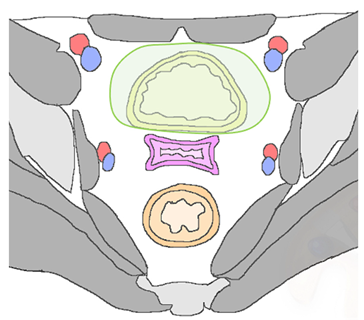

| Type of Recurrence | Imaging Findings |

|---|---|

| Local | |

Cervix, parametria, or vaginal cuff![]() |

|

| Regional | |

| Anterior Urinary bladder and urethra ![]() |

| Posterior Rectal or sigmoid colon ![]() | An infiltrating, spiculated mass, causing rectal or sigmoid luminal narrowing.

| Lateral Pelvic sidewall ![]() | Pelvic sidewall recurrence is defined as a tumor extending within 3 mm and abutting the obturator internus or piriformis muscles with concomitant loss of fat planes. Other findings include:

| Lymphadenopathies | |

| Paracervical, parametrial, internal and external iliac, obturator, sacral, common iliac and para-aortic lymph nodes. |